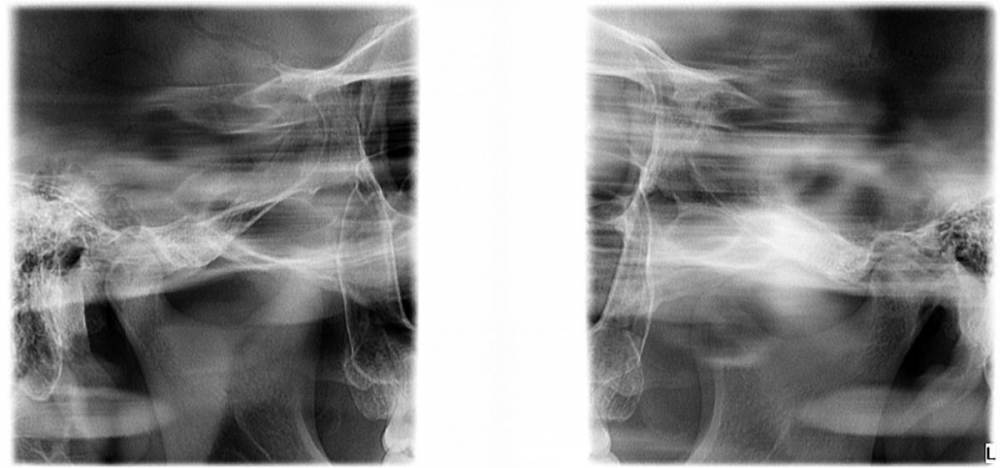

smikvarnik Опубликовано 12 июня, 2023 Поделиться Опубликовано 12 июня, 2023 (изменено) Здравствуйте, проблема следующая 25 лет, пол М У меня с детства аномалии(нет корней на 3х зубах), одна двойка справа молочная + тройки молочные. Двойка выпала и хожу с дыркой уже лет 10, также зона улыбки кривовата и есть промежуток между однерками тройки молочные маленькие но держатся, все хорошо. Самая главная проблема по которой мне многие отказывали в реставрации только зоны улыбки, это прикус. у меня глубокий прикус с детства. Ортодонты говорят что нужно носить брекеты 2-3 года, и только после этого имплантация либо коронки с мостами. Но пару ортопедов предложили мне сточить все верхние зубы(все жевательные зубы в отличном состоянии, передние так себе, уже немного сточены из за прикуса). Говорят что если поставить без исправления прикуса - я просто выбью коронки или импланты, нагрузка будет не такая какая должна быть Пробовал также ходить с капой чтобы поднять прикус - результатов нет. некоторые врачи отказывали даже в лечении брекетами, говоря что ситуация сложная. Также зубы для моего возраста маленькие, по сравнению с другими людьми Говорят что если сделать коронки на верхней челюсти, можно таким образом исправить прикус+сделать улыбку без ортодонтии. но также возможно потребуется сточить немного зубов на нижней(не уточнял какие) Коронки из диоксида циркония как вы считаете, это нормальный вариант, или так себе? у меня психологический комплекс из за зубов и еще 2-3 года ходить с брекетами и дырками честно говоря так себе идея. Какие есть минусы и опасности у такого варианта, и как с вашей точки зрения, как докторов, этот вариант оценивается? Насколько это целесообразно? Спасибо за помощь заранее, очень жду ответ, каждый день волнует эта тема Изменено 12 июня, 2023 пользователем smikvarnik Ссылка на комментарий

smikvarnik Опубликовано 13 июня, 2023 Автор Поделиться Опубликовано 13 июня, 2023 здравствуйте, не видел! исправляю еще также есть фото лица и самих зубов, как попросите так и сфоткаю. также есть КТ ВЧ и НЧ Ссылка на комментарий